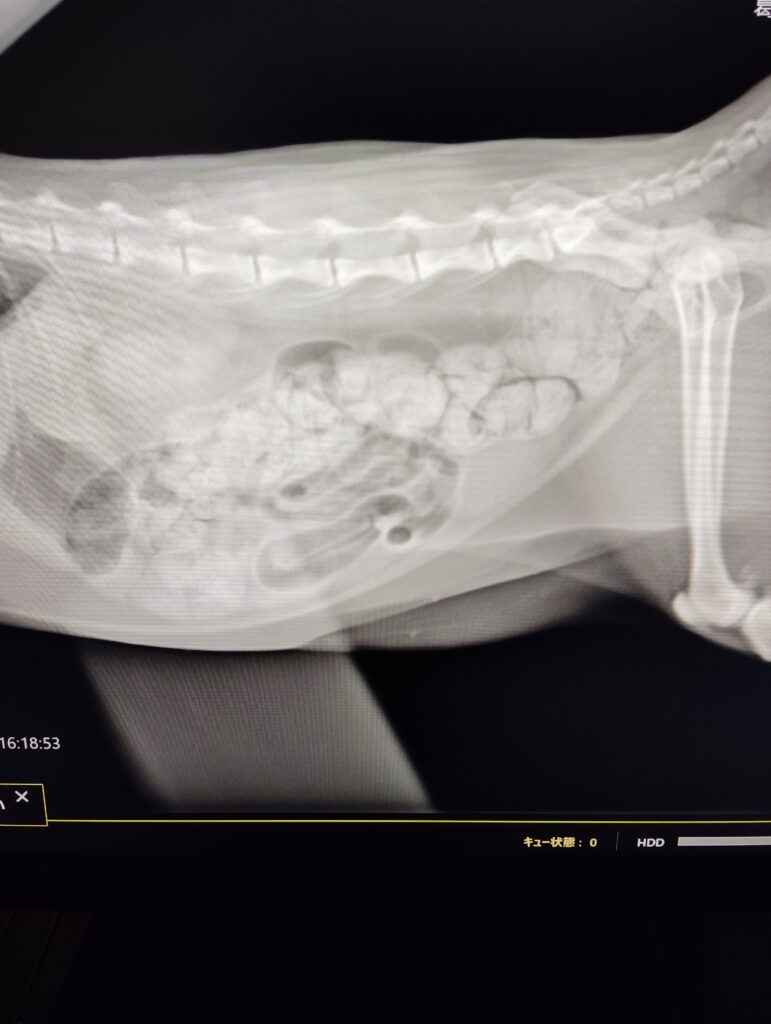

- 腹部触診で結腸部に硬い糞便を触知

- レントゲン検査にて結腸拡張(便塊の貯留)を確認

→ 診断:慢性便秘